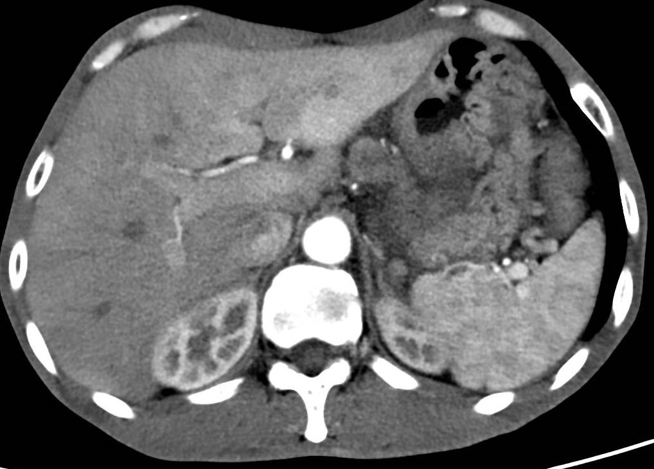

颅脑MRI(2024年8月6日)检查提示双侧额叶占位性病变,考虑脑脓肿可能性大(图2)。

图片2.png图2. 颅脑MRI检查(2024年8月6日)

为控制颅内感染,患者于2024年8月29日在全麻下行脑脓肿切除术,术后病理证实为脑脓肿。术后复查头部MRI显示病灶明显改善。